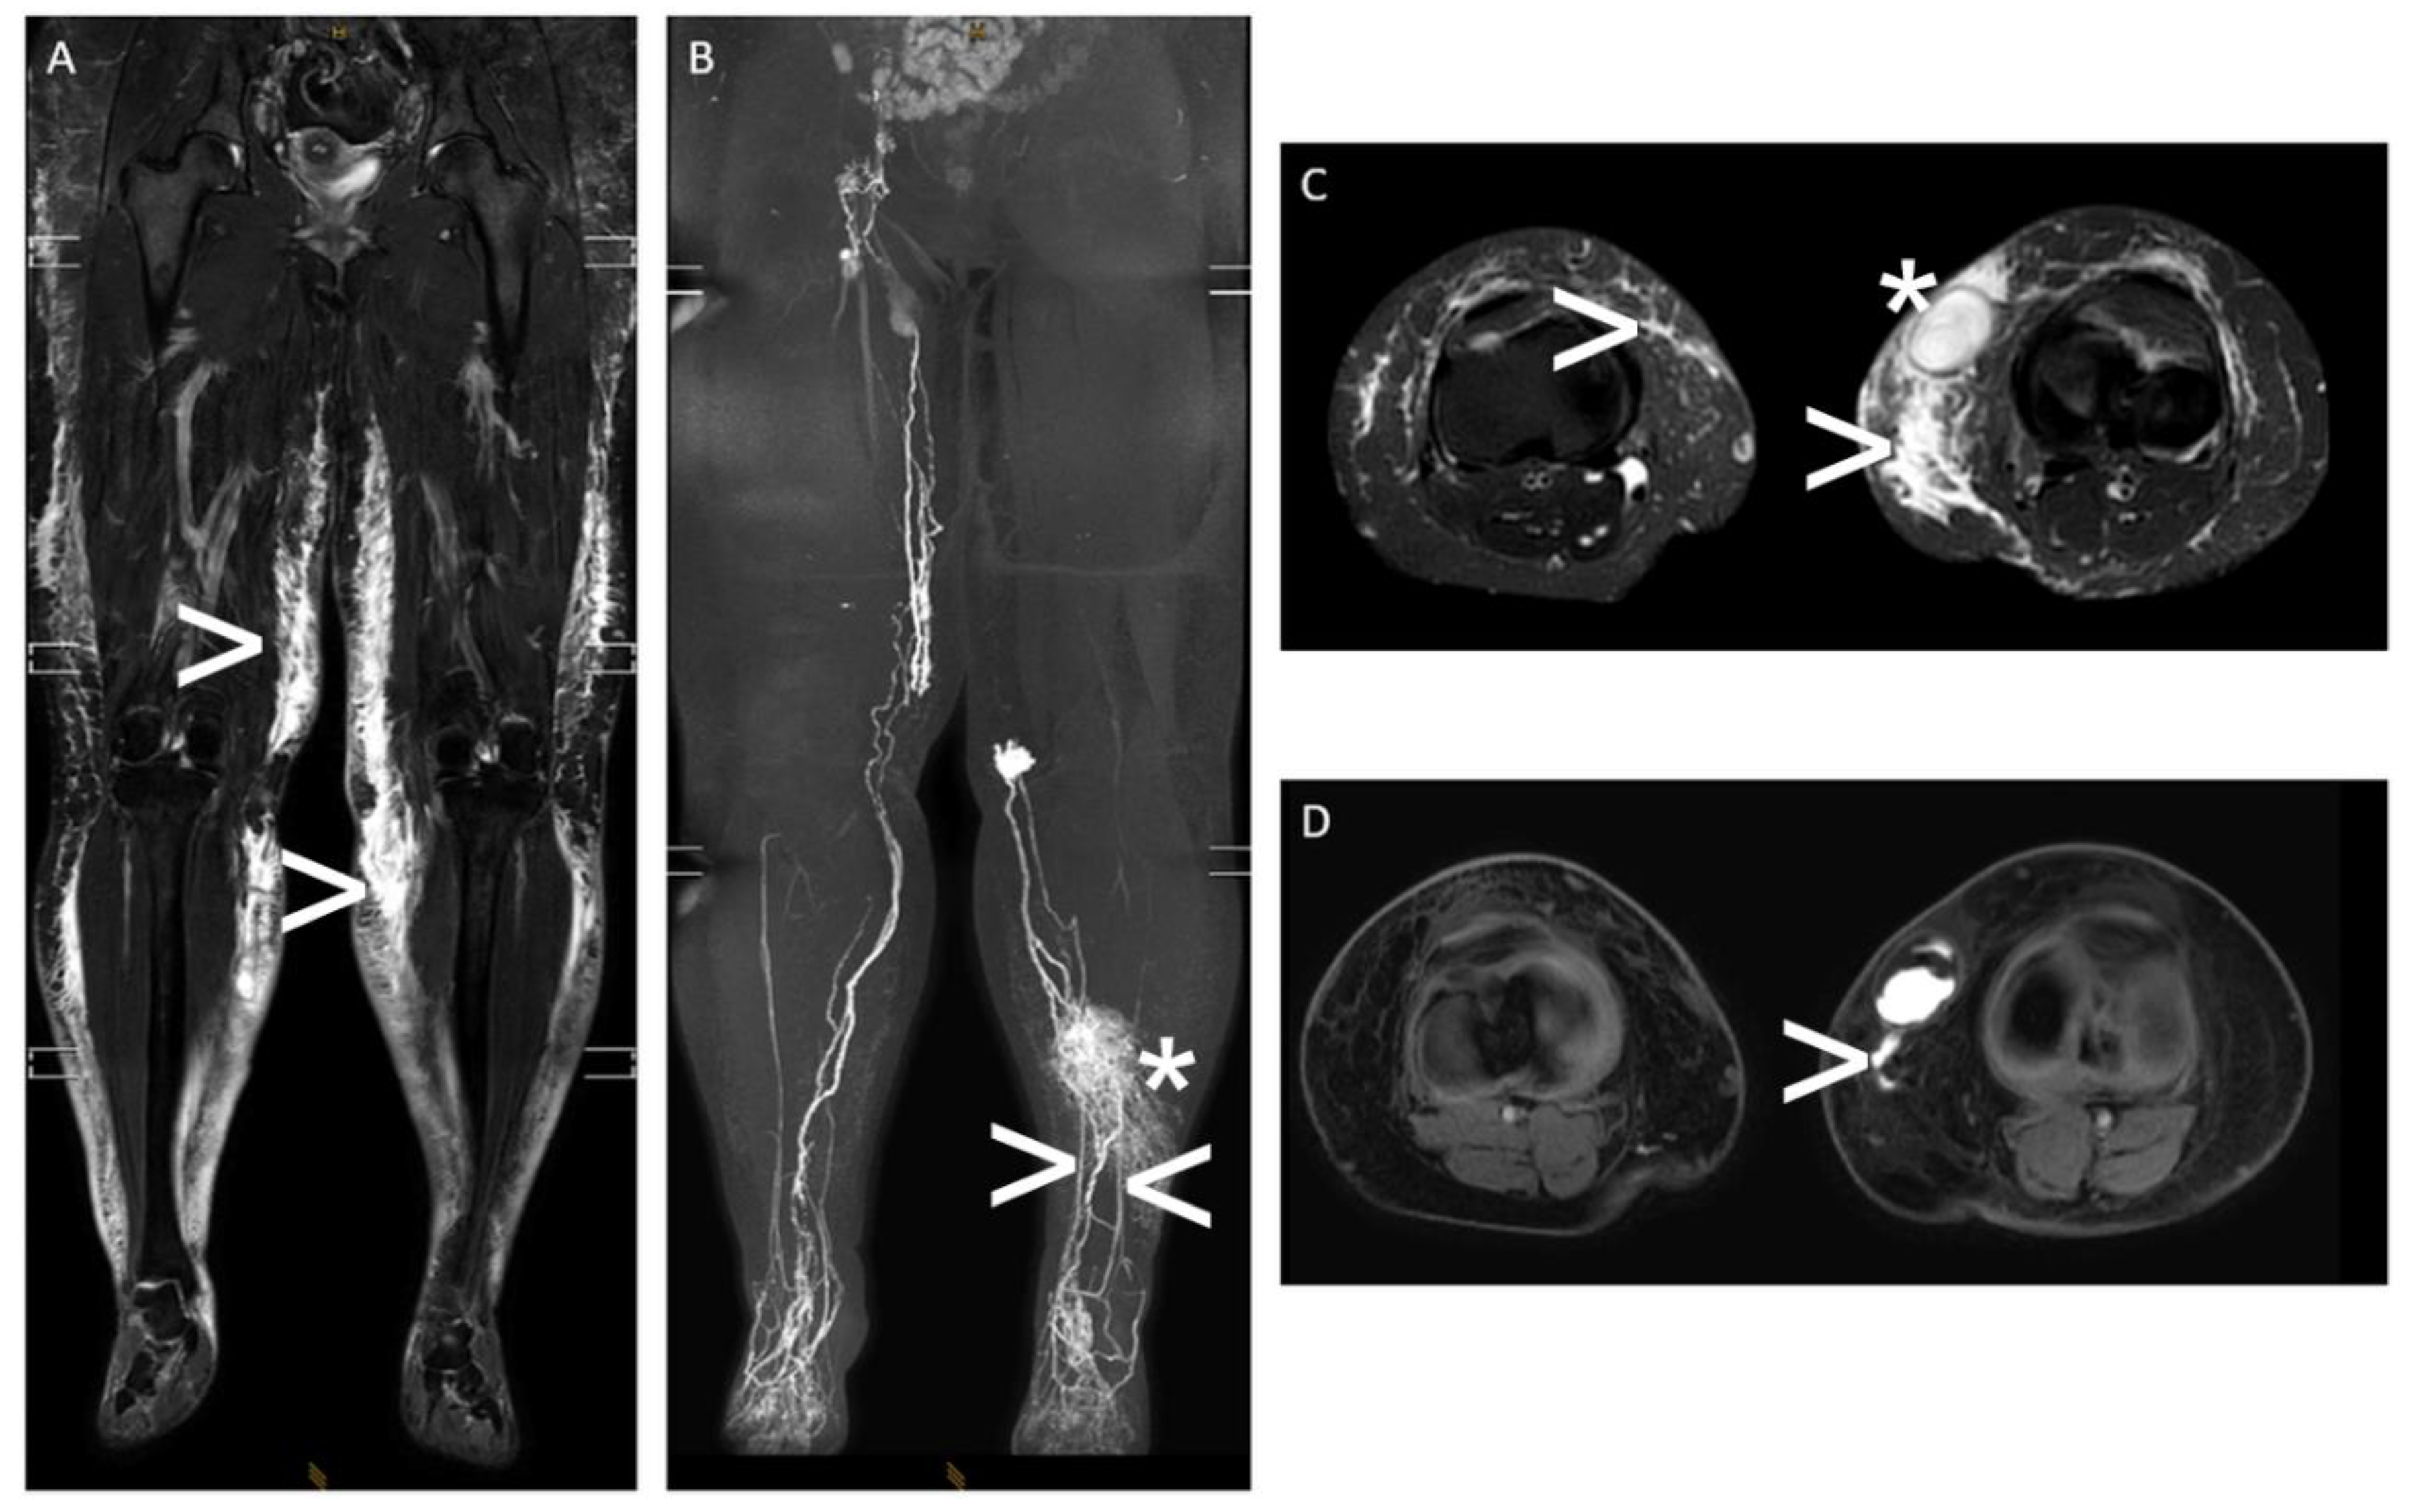

Figure 6.

“Interstitial MR lymphangiography“—A 43-year-old woman with massive lymphedema of both legs and a refractory superficial lymphocele medial to the left knee with an intermittent cutaneous lymphatic fistula after multiple plastic surgeries of the legs. Note: (A,C) T2-weighted, fluid-sensitive MRI ((A): coronal plane and (C): axial plane) showing subcutaneous lymphedema of both legs (white arrowhead) and the lymphocele of the left leg (white asterisk); (B,D) contrast material (gadolinium)-enhanced “interstitial MR lymphangiography” (B): coronal maximum-intensity projection and (D): axial plane showing impaired lymphatic run-off of both legs with dilated superficial lymph ducts, dermal reflux on the left (white asterisk), and active lymphatic fistula draining into the lymphocele on the left with two superficial lymphatic feeders (white arrowhead).